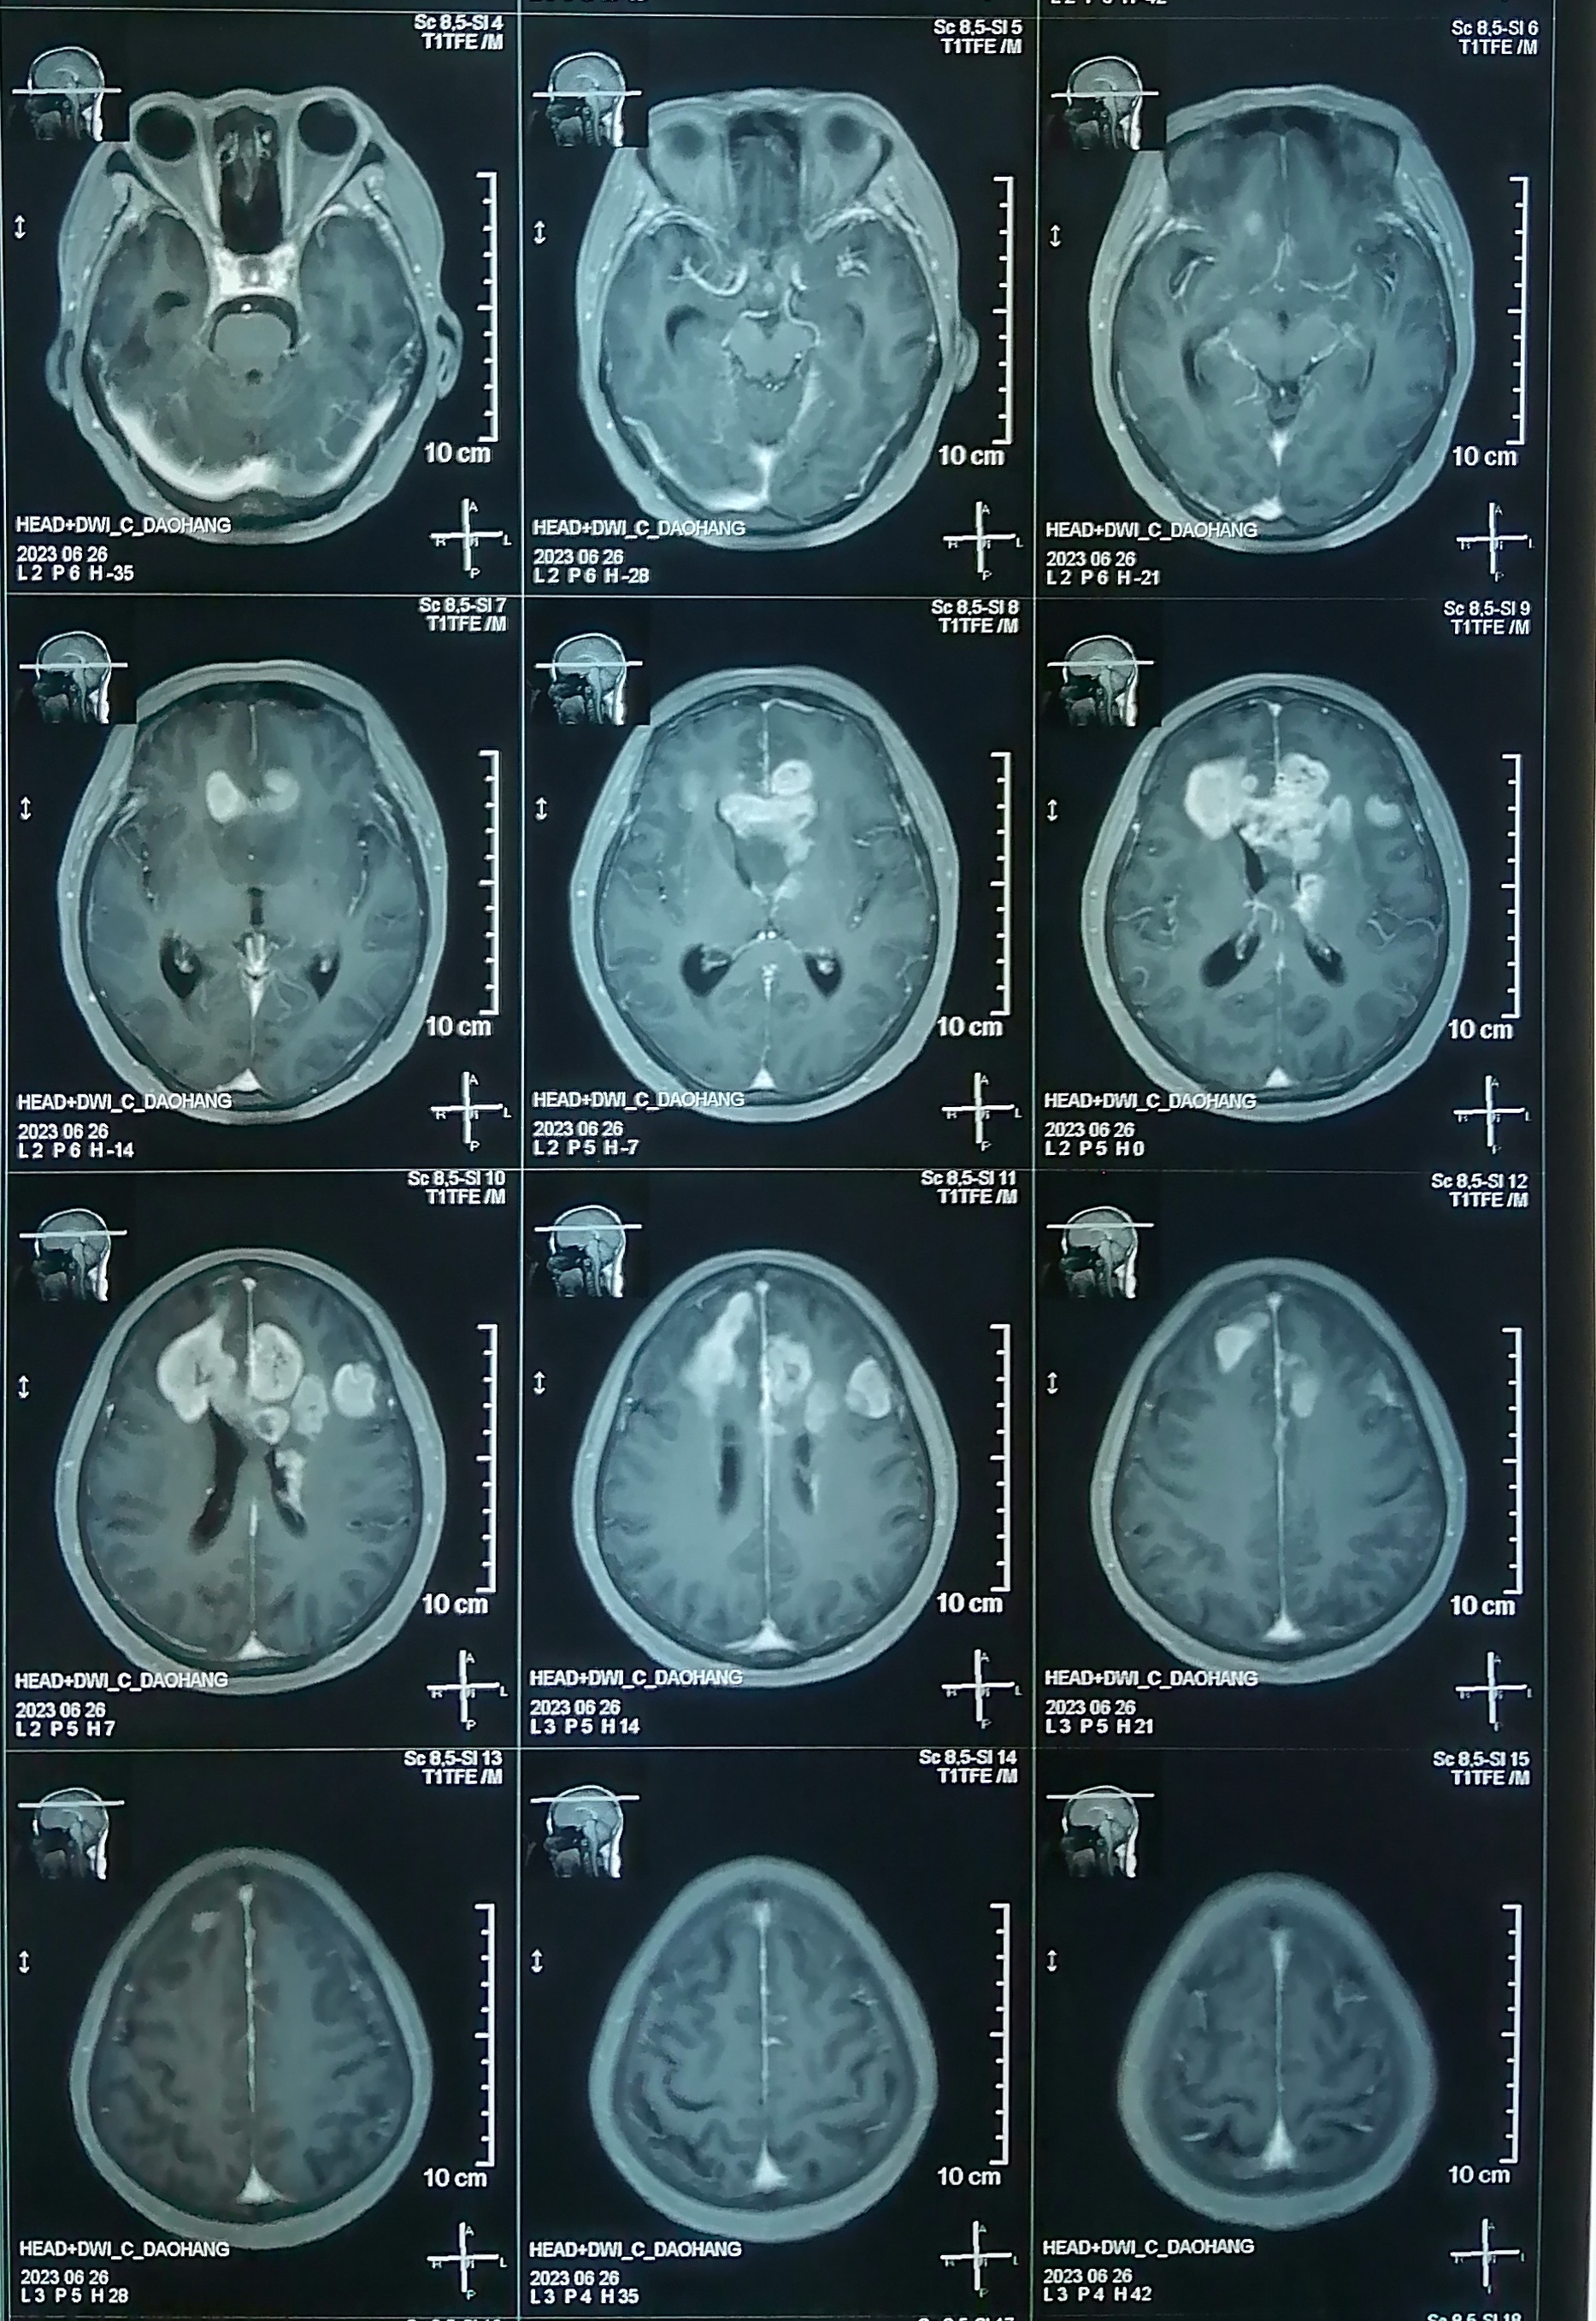

术前增强核磁:

片子可见肿瘤多中心, 累及范围广,包括胼胝体膝部,穹窿体,下丘脑,双侧额叶,左侧脑室前壁。